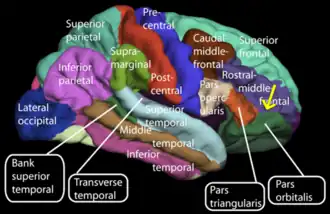

Lateral view of a human brain showing main gyri labeled.

Lateral view of a human brain showing main gyri labeled. -

Animated view of orbital part of inferior frontal gyrus

Animated view of orbital part of inferior frontal gyrus